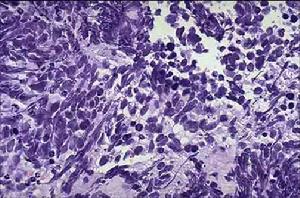

(一)鱗狀上皮細胞癌(簡稱鱗癌)

鱗狀包括梭形細胞癌,是最常見的類型,約占原發性肺癌40%-50%。多見於老年男性,與吸菸關係非常密切。以中央型肺癌多見,並有向管腔內生長的傾向,常早期引起支氣管狹窄,導致肺不張,或阻塞性肺炎。癌組織易變性、壞死,形成空洞或癌性肺膿腫。鱗癌生長緩慢,轉移晚,手術切除的機會相對多,5年生存率較高,但對放射治療(簡稱放療)、化學藥物治療(簡稱化療)不如小細胞未分化癌敏感。

由於支氣管黏膜柱狀上皮細胞受慢性刺激和損傷、纖毛喪失、基底細胞鱗狀化生、不典型增生和發育不全,最易突變成癌。典型的鱗癌細胞大,呈多形性,胞漿豐富,有角化傾向,核畸形,染色深,細胞間橋多見,常呈鱗狀上皮樣排列。電鏡檢查,癌細胞間有大量核粒和張力纖維束相連線。

(二)小細胞未分化癌(簡稱小細胞癌)

小細胞癌包括燕麥細胞型、中間細胞型、符合燕麥細胞型。是肺癌中惡性程度最高的一種,占原發性肺癌的10%-15%。患者年齡較輕,多在40-50歲左右,多有吸菸史。多發生於肺門附近的大支氣管,傾向於黏膜小層生長,常侵犯管外肺實質,易與肺門、縱隔淋巴結融合成團塊。癌細胞生長快,侵襲力強,遠處轉移早。手術時發現60%-100%血管受侵犯,屍檢證明80%-100%有淋巴結轉移,常轉移至腦、肝、骨、腎上腺等臟器。本型對放療和化療比較敏感。

癌細胞多為類圓形和棱形,胞漿少,類似淋巴細胞。燕麥細胞型和中間型可能起源於神經外胚層的Kulchitsky為細胞或嗜銀細胞。核細、胞漿內含有神經分泌型顆粒,具有內分泌和化學受體功能,能分泌5-羥色胺、兒茶酚胺、組胺、激肽等肽類物質,可引起副癌綜合徵。

(四)腺癌

腺癌包括眼泡狀、乳頭狀、細支氣管-肺泡癌和實體瘤伴粘液形成。女性多見,災難性亦有增多趨勢。與吸菸關係不大,多生長在肺邊緣小支氣管的粘液腺,因此在周圍型肺癌中以腺癌為最常見。腺癌約占原發性肺癌25%。腺癌傾向於管外生長,但也可循泡壁蔓延,常在肺邊緣部形成直徑2-4cm的腫塊。腺癌富血管,故局部浸潤和血行轉移較鱗癌早。易轉移至肝、腦和骨,更易累及胸膜而引起胸腔積液。

典型的腺癌細胞,呈腺體或乳頭狀結構,細胞大小比較一致,圓形或橢圓形,胞漿豐富,常含有粘液,核大,染色深,常有核仁,核膜比較清楚。